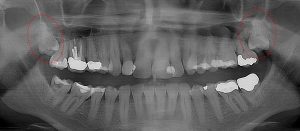

This 48 year old patient had all four 3rd molars extracted in his late 20’s. All four sites healed poorly and chronically infected bony defects remained. The upper right 2nd molar was extracted two years ago as a result of this chronic infection. The upper left 2nd molar must now be extracted because of a chronic periodontal infection moving around that tooth. Both lower molars are chronically infected and have a poor prognosis.